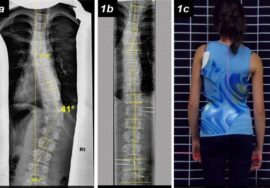

كيف يتم تحديد عدد انحناءات اعوجاج العمود الفقري طبيًا؟

الطريقة الوحيدة الدقيقة لمعرفة عدد الانحناءات هي الفحص الطبي المدعوم بالأشعة.

الأشعة السينية

الأشعة السينية هي الأساس في تحديد:

• عدد الانحناءات

• موقع كل انحناء (صدري، قطني، أو مختلط)

• اتجاه الانحناء

• درجة كل انحناء على حدة

من خلال الأشعة يمكن رؤية العمود الفقري بالكامل وتحديد كل انحناء بوضوح.